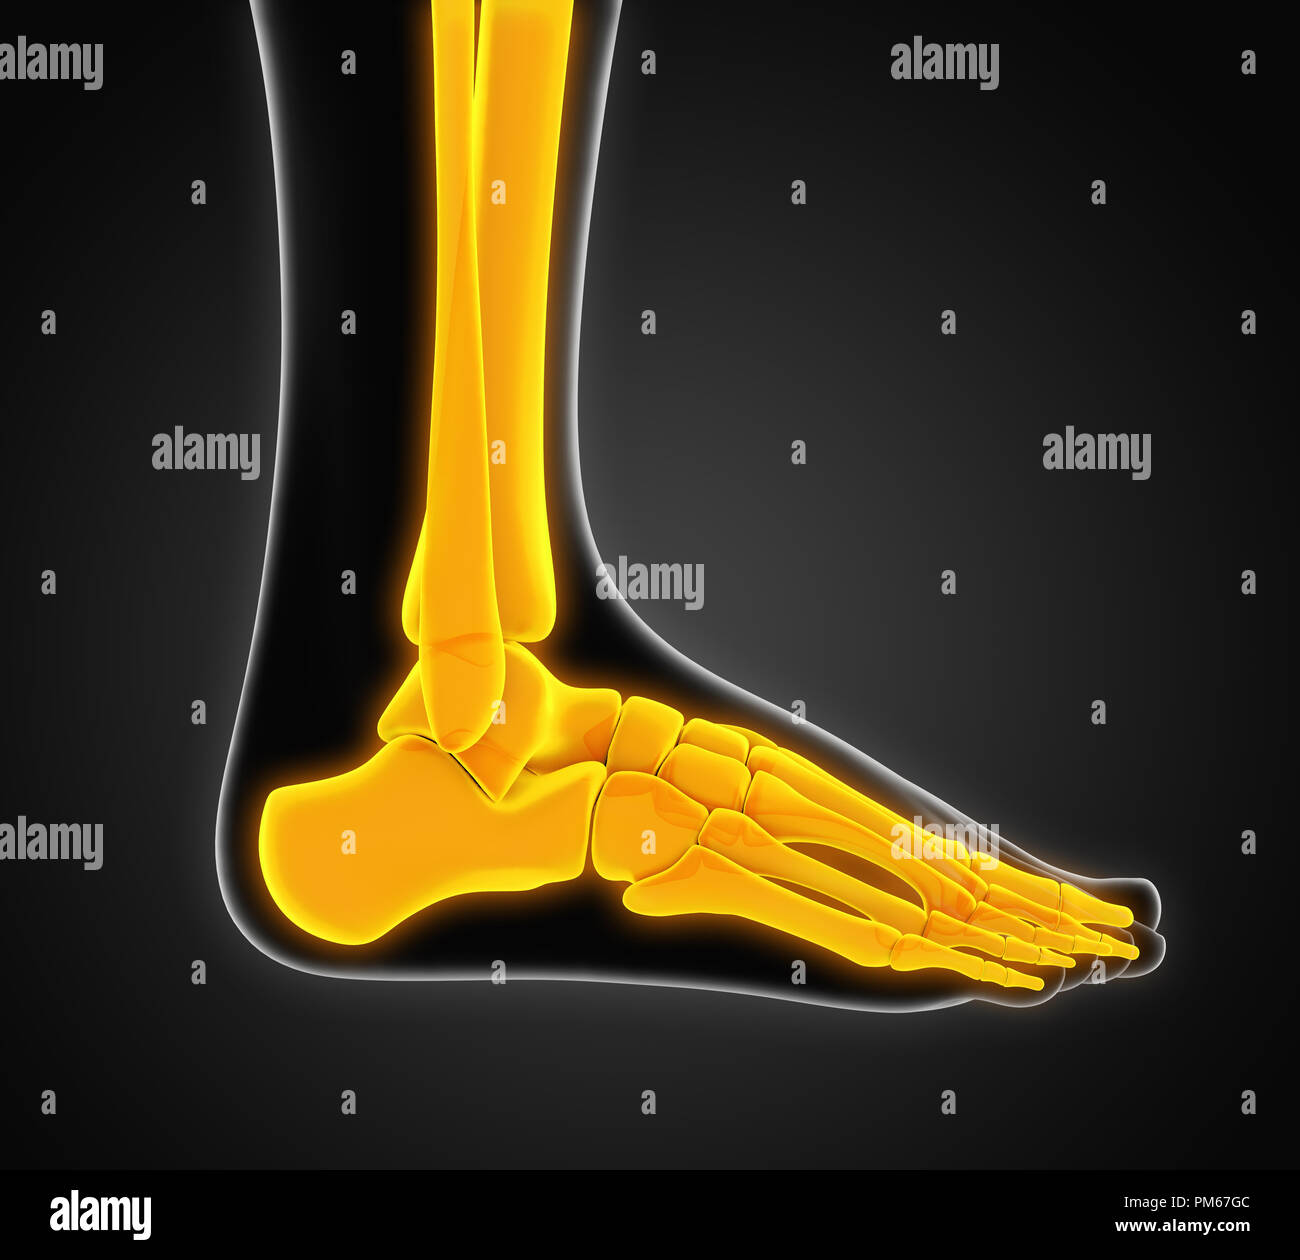

RF2R3WKY1–Illustration médicale des principales parties des os du pied en vue latérale, avec annotations.